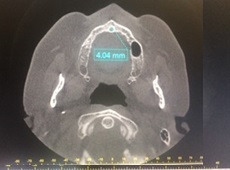

La primera medida perpendicular se obtuvo en el corte sagital oblicuo a nivel inferior del CNP situado desde la cortical interna hasta la cortical externa de su pared anterior. La segunda medida se obtuvo a nivel medio del mencionado conducto, equidistante entre la porción superior e inferior, situado desde la cortical interna y externa. La tercera medida se obtuvo a nivel superior de la pared anterior del CNP, a nivel del piso de fosas nasales y de cortical interna a cortical externa. La medida vertical se realizó desde la medida superior a la inferior horizontal en el centro de la luz del conducto (ver imagen 1 y 3). La medida transversal se obtuvo en un corte axial a nivel de un punto equidistante entre superior e inferior (ver imagen 2 y 4).

Se observa la medida del diámetro transversal del CNP

fotografía autores

fotografía autoresResultados

En los pacientes dentados el promedio del diámetro a nivel inferior es de 2,5mm, a nivel medio es de 1,75mm y superior es de 2,33mm. El promedio de la altura es de 10,68mm y el diámetro transversal es de 3,45mm (Tabla 1 y Gráfico 1). En los pacientes edéntulos el promedio del diámetro a nivel inferior es de 3,55mm, a nivel medio es de 2,55mm y superior es de 3,01mm. El promedio de la altura es de 7,9mm y el diámetro transversal es de 4,55mm (Tabla 2 y Gráfico 2).